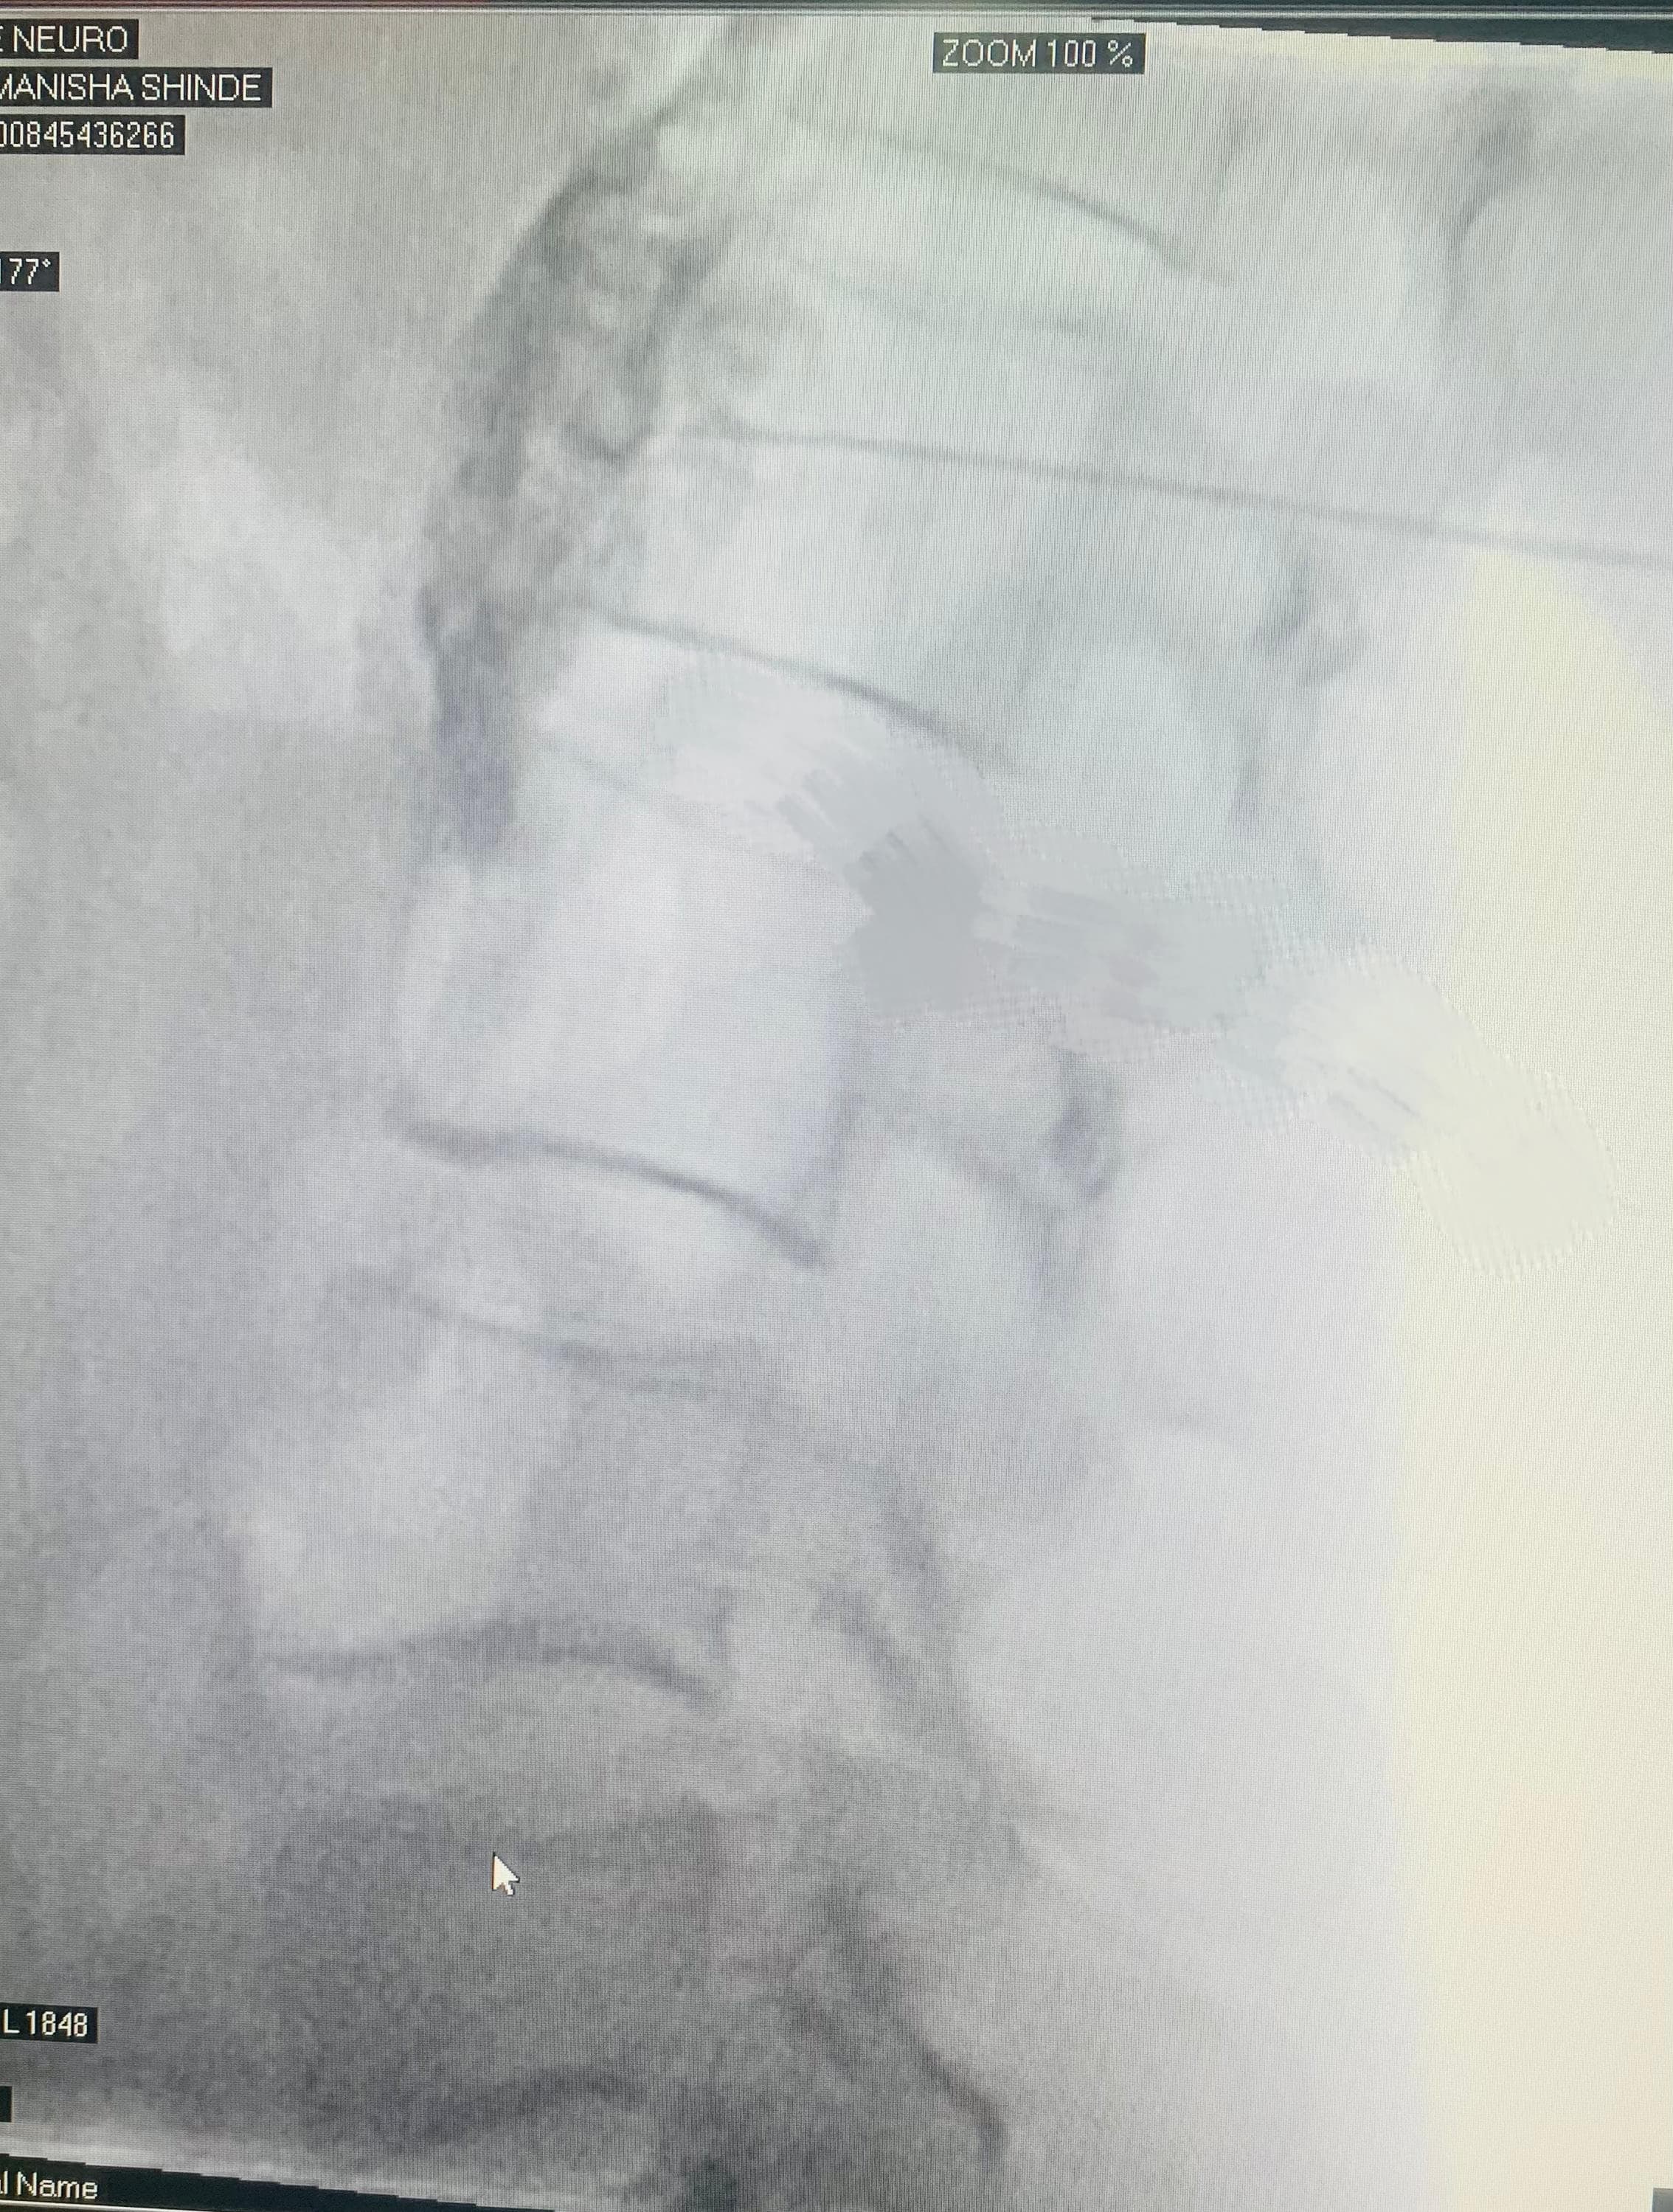

Patient Guide: Lumbar Sympathetic Block By Dr. Pri...